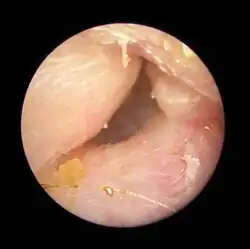

Exostoses in the ear canal, as seen through otoscopy | |

Surfer's ear is the common name for an exostosis or abnormal bone growth within the ear canal. They are otherwise benign hyperplasias (growths) of the tympanic bone thought to be caused by frequent cold-water exposure.[1] Cases are often asymptomatic.[1] Surfer's ear is not the same as swimmer's ear, although infection can result as a side effect.

Irritation from cold wind and water exposure causes the bone surrounding the ear canal to develop lumps of new bony growth which constrict the ear canal. Where the ear canal is actually blocked by this condition, water and wax can become trapped and give rise to infection. The condition is so named due to its high prevalence among cold water surfers, although it can occur in any water temperature due to the evaporative cooling caused by wind and the presence of water in the ear canal.

In general, one ear will be somewhat worse than the other due to the prevailing wind direction of the area surfed[3] or the side that most often strikes the wave first. Common symptoms include recurrent otitis externa, obstructed sensation, conductive hearing loss, pain in the ear, and tinnitus.[1]